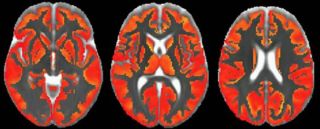

InvestigaciónCuanto antes se controlen los factores de riesgo cardiovascular, mejor para el cerebro, según un estudioUn estudio publicado en ‘The Lancet Healthy Longevity’ muestra que las personas de mediana edad con un riesgo cardiovascular elevado de forma sostenida durante cinco años experimentan una mayor disminución del metabolismo cerebral. Por ello, según los autores de la investigación, cuanto antes se controlen los factores de riesgo de las enfermedades cardiovasculares, mejor para el cerebro, ya que podría prevenirse el desarrollo de demencias